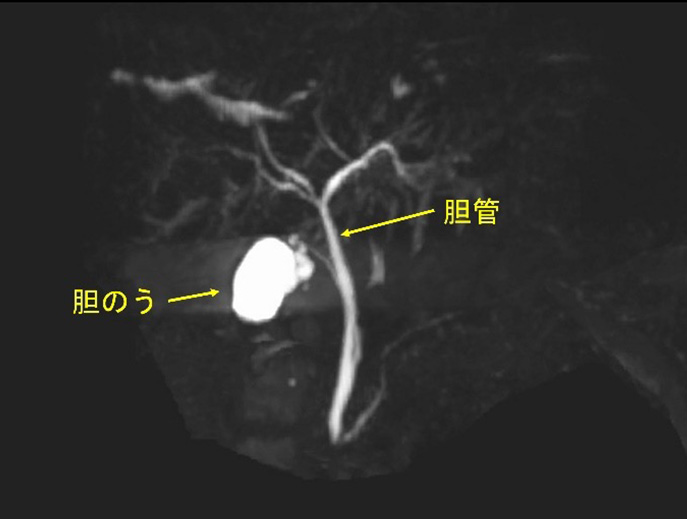

経口胆嚢造影は、胆嚢のX線検査です。胆嚢は、腹腔の右上、肝臓のすぐ下に位置する臓器です。肝臓によって生成される液体である胆汁を貯蔵し、食事からの脂肪の消化と吸収を助けます。

経口胆嚢造影検査は、胆嚢がんや肝臓の胆管系における胆汁の流れの減少または遮断など、胆嚢に関連する問題を診断するために使用されます。